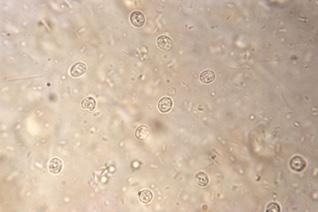

Microbiología: tinción ácido-resistente, PCR y cultivo